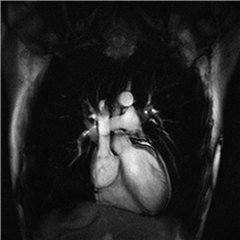

Pourquoi les personnes en surpoids sont-elles plus à risque de troubles cardiaques ? L’une des clés de ce lien délétère se trouve dans les cellules du muscle cardiaque, en particulier dans leurs mitochondries, selon les travaux de Jérémy Fauconnier, directeur de recherche CNRS dans le laboratoire montpelliérain PhyMedExp.